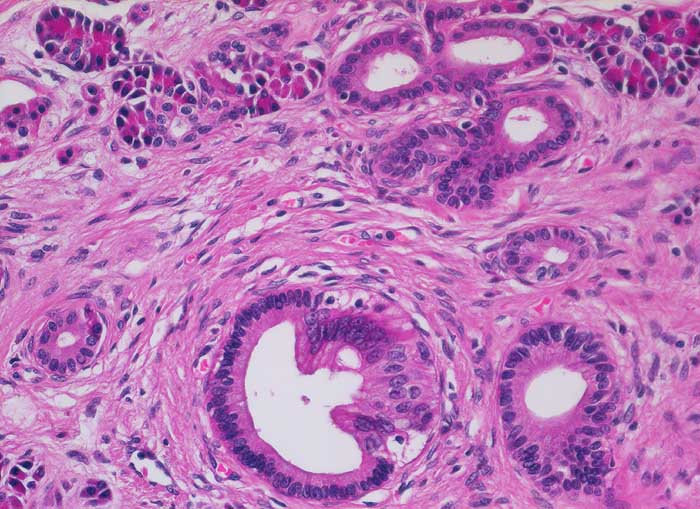

Chronisch-sklerosierende Pankreatitis

Die Azini sind in ihrer Anzahl vermindert und partiell ersetzt durch dichtes Bindegewebe. Die Gangstrukturen sind im Gegensatz zu Karzinomdrüsen schön ausgeformt und die auskleidenden Epithelzellen weisen keinerlei Atypien auf.

Alkoholiker mit rezidivierten akuten Pankreatitisschüben. Chronische Diarrhoe.